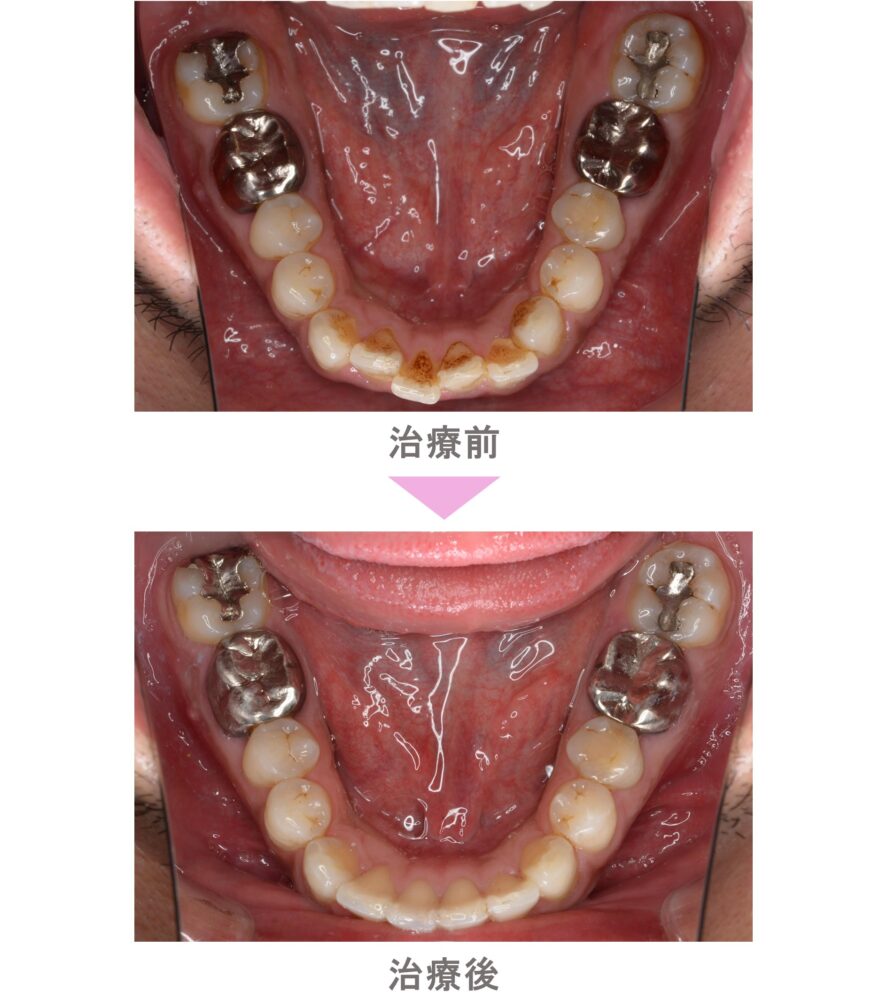

裏側矯正(舌側矯正)の症例のご紹介です。この患者様は、東京都世田谷区からご来院の中学生女子で、叢生(前歯のでこぼこ)と八重歯(犬歯突出)と交叉咬合(すれ違い)の症状がありました。治療法は裏側矯正(舌側矯正)。非抜歯で矯正治療を行い、キレイな歯並びになりました。治療期間は11か月です。